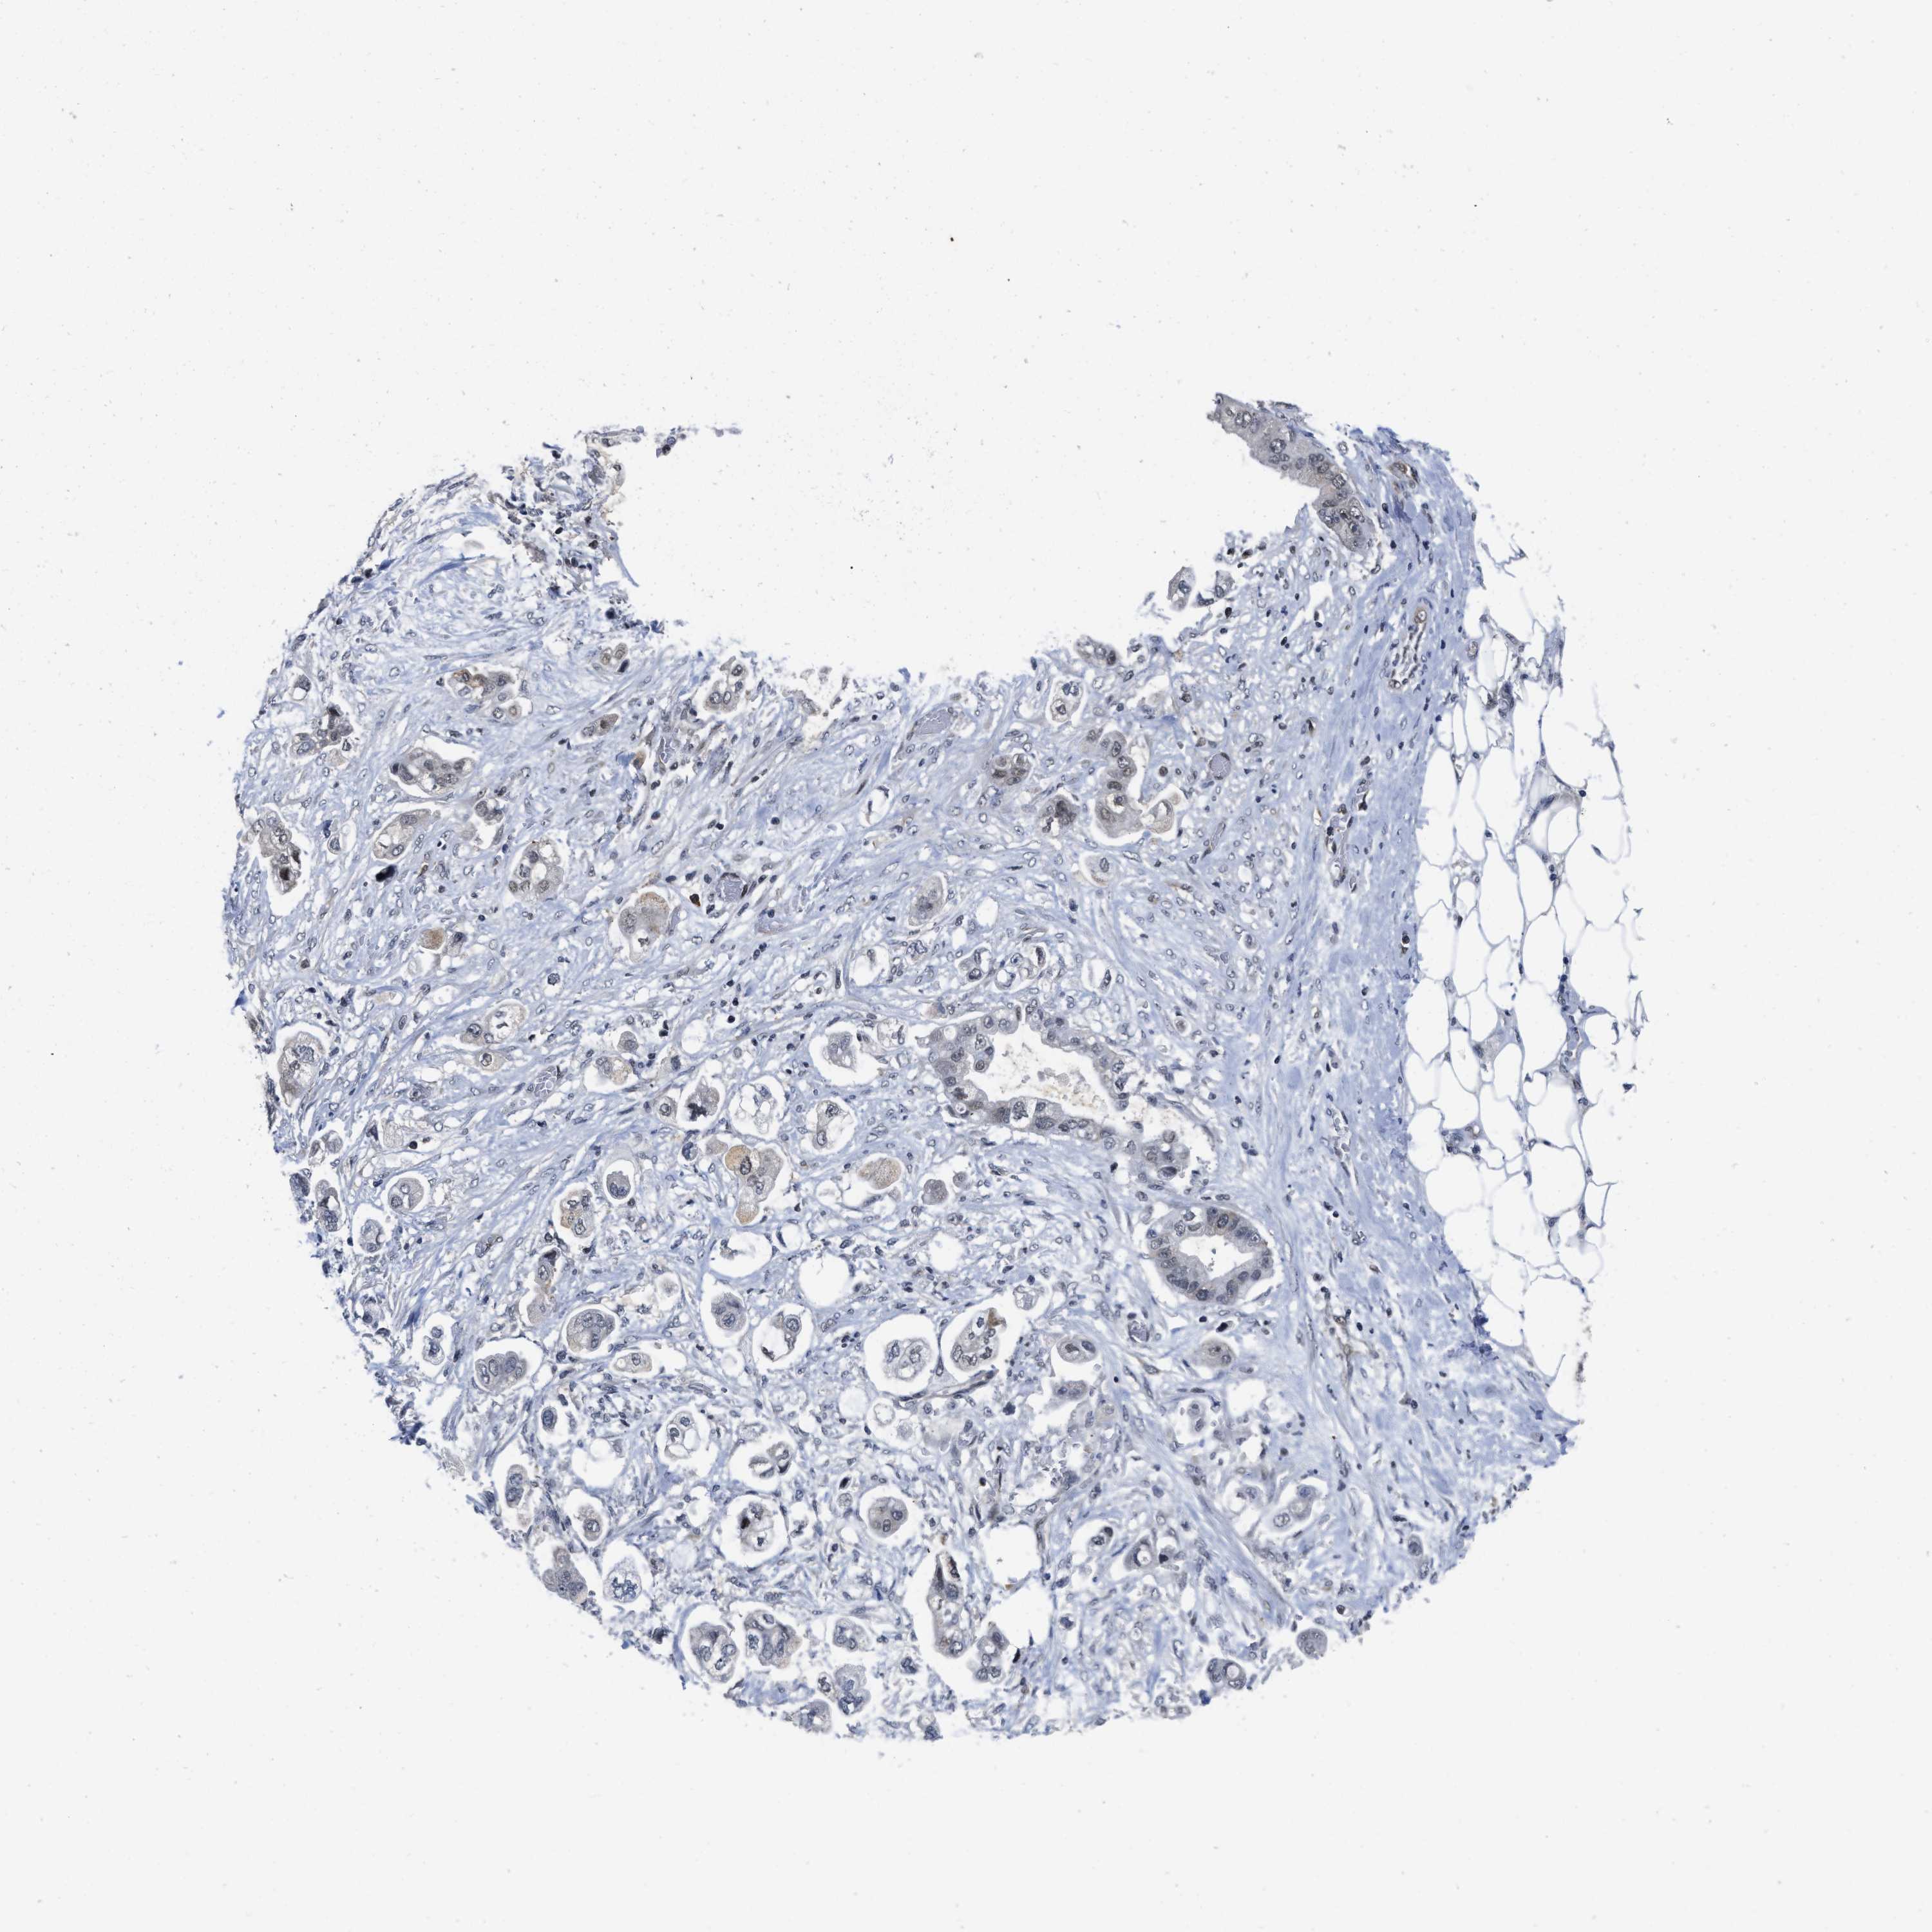

STOMACH CANCER - Protein expressioni

A mouse-over function shows sample information and annotation data. Click on an image to view it in a full screen mode. Samples can be filtered based on level of antibody staining by selecting one or several of the following categories: high, medium, low and not detected. The assay and annotation is described here.

Note that samples used for immunohistochemistry by the Human Protein Atlas do not correspond to samples in the TCGA dataset.

Antibody stainingi

Antibody staining in the annotated cell types in the current human tissue is reported as not detected, low, medium, or high, based on conventional immunohistochemistry profiling in selected tissues. This score is based on the combination of the staining intensity and fraction of stained cells.

Each image is clickable and will lead to virtual microscopy that enables deeper exploration of all samples and also displays staining intensity scores, fraction scores and subcellular localization as well as patient and tissue information for each sample.

Antibody HPA001275

Antibody CAB017442

Staining

High

Medium

Low

Not detected

Intensity

Strong

Moderate

Weak

Negative

Quantity

>75%

75%-25%

<25%

None

Location

Nuclear

Cytoplasmic/membranous

Cytoplasmic/membranous,nuclear

Adenocarcinoma, NOS